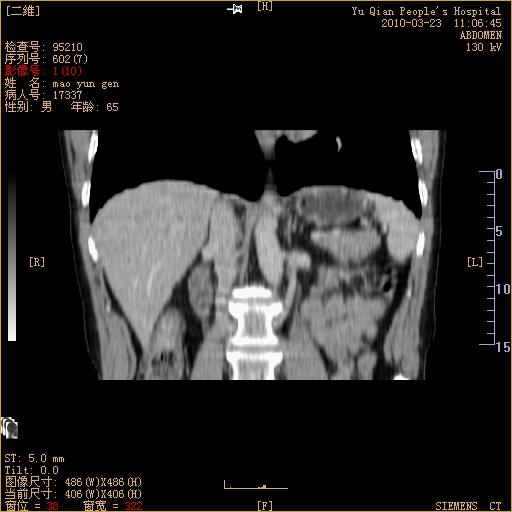

标题: CT25266:消瘦月余,前来肝部检查,请看看肠腔 [打印本页]

标题: CT25266:消瘦月余,前来肝部检查,请看看肠腔

升结肠肠壁增厚,不均强化,考虑升结肠腺癌可能性,建议肠镜检查。

1)考虑升结肠癌。2)右肾小囊肿。